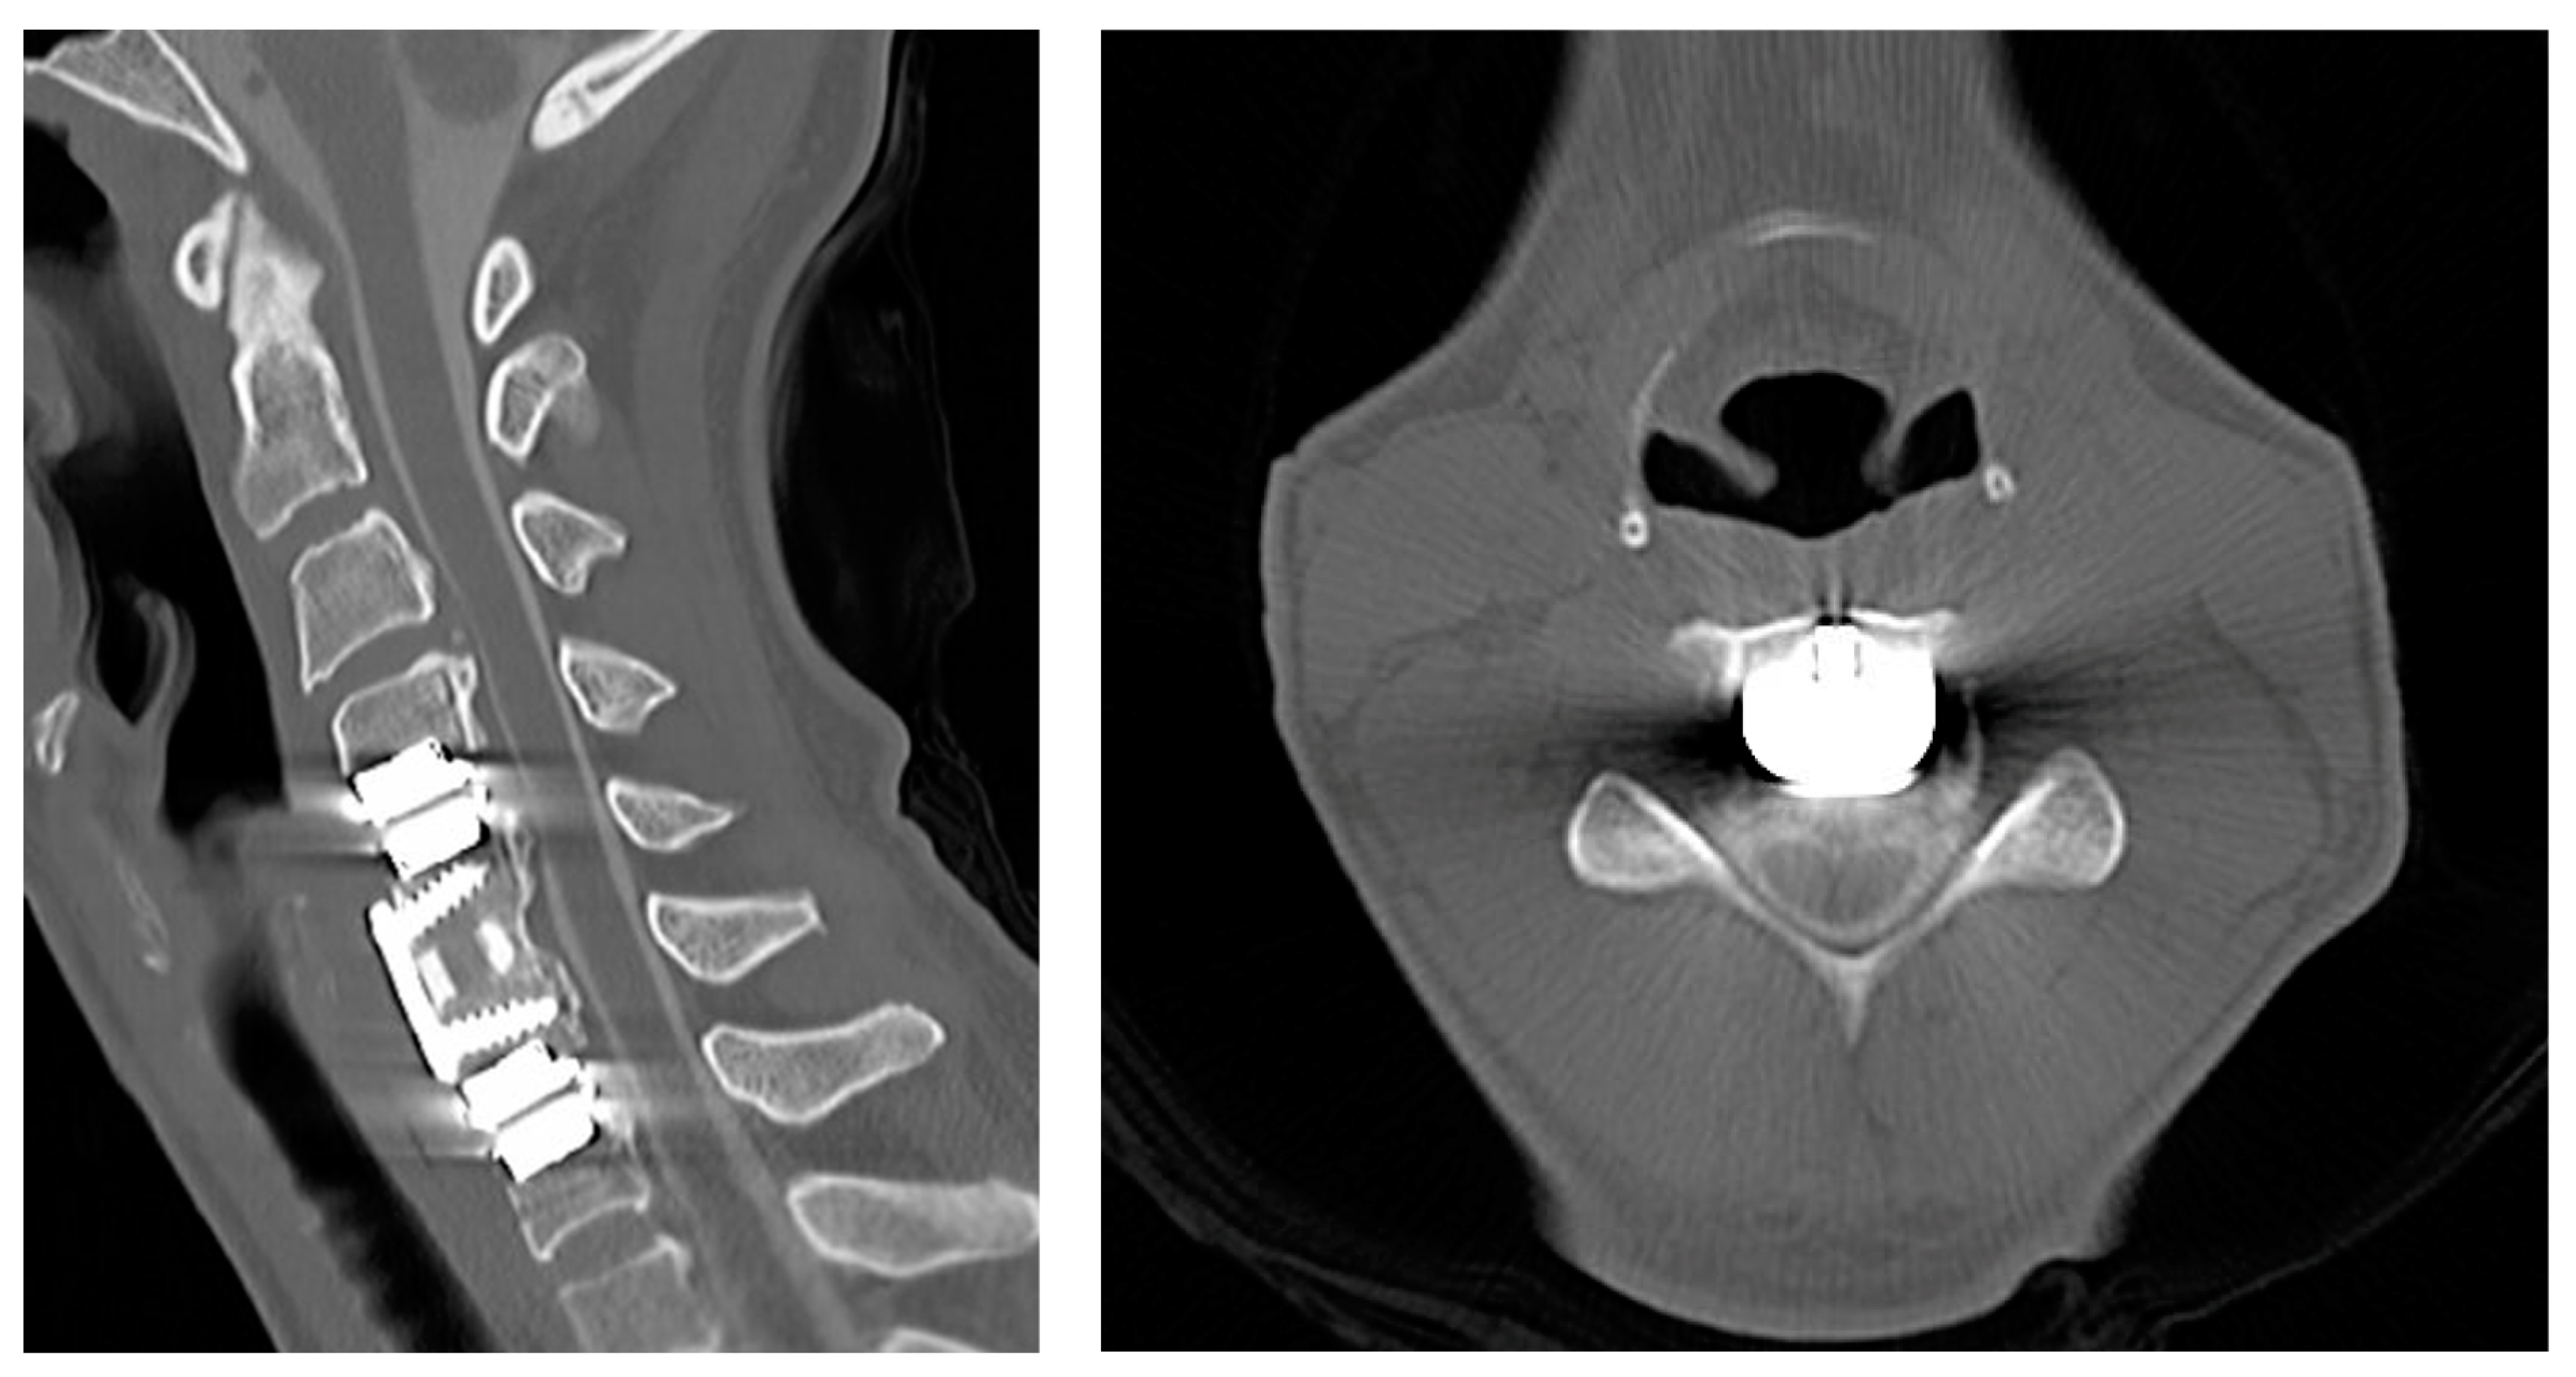

2.1. Case 1